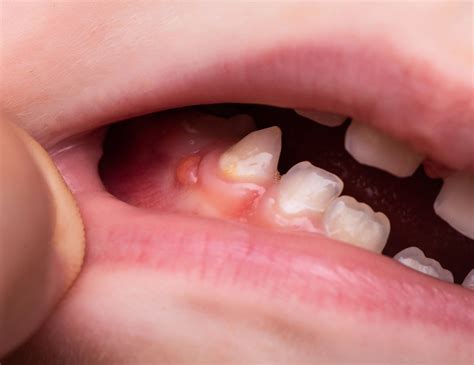

Llamamos fístula dental al canal que se origina desde la zona infectada de un diente hasta la superficie exterior de la encía. Una fístula dental es una afección oral que implica la formación de un conducto anormal entre el diente y el exterior de la boca. Esta conexión anormal se crea como resultado de una infección dental que ha progresado y se ha extendido más allá de la raíz del diente, formando un absceso. En ese canal se acaba depositando pus y, conforme se llena, se crea una protuberancia o grano próximo a las encías. El pasaje actúa como depósito de pus y a medida que se llena, se forma una pequeña protuberancia en forma de grano cerca de las encías.

Es el propio organismo quien crea esta fístula, y lo hace tras detectar una infección dental. La fístula actúa como un conducto de drenaje para permitir que el pus y los desechos de la infección se eliminen del cuerpo. En dicha fístula se alberga el pus que se genera y que no somos capaces de drenar. Por lo tanto, aunque es una dolencia bucodental y una infección, también es un mecanismo que sirve de alerta.

Una fístula dental es una pequeña abertura o canal anormal que se forma en la encía o en la región cercana a la raíz de un diente infectado. La creación de una fístula dental se produce debido a la propagación de una infección en el diente o en los tejidos circundantes. Normalmente, la infección se origina en el interior del diente, en la pulpa dental, donde se encuentra el tejido blando, los nervios y los vasos sanguíneos.